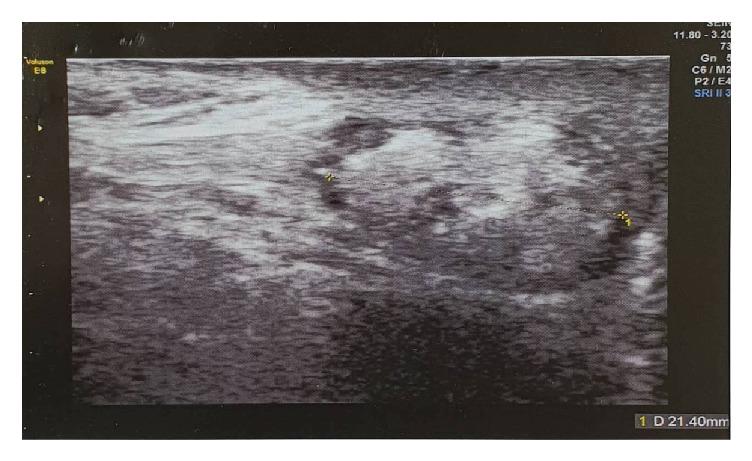

We report a rare case of paratesticular angiolipoma in a young male. The patient is a 21-year-old male who presented with a palpable firm right intrascrotal mass of 21 mm. Ultrasound findings demonstrated that it is a solid mass. Under the diagnosis of an intrascrotal solid mass, a right inguinal radical orchiectomy was performed. Histopathological examination concluded to a paratesticular angiolipoma. Angiolipoma is a rare benign form of paratesticular tumour and its diagnosis is based on histological findings of the surgical specimen with no recurrence risk. This mesenchymal tumour should be distinguished from liposarcoma, which has malignant or aggressive clinical course.

我们报告一例年轻男性睾丸旁血管脂肪瘤的罕见病例。患者为21岁男性,右侧阴囊内可触及一个21毫米的实性肿物。超声检查结果显示这是一个实性肿块。在诊断为阴囊内实性肿块后,进行了右侧腹股沟根治性睾丸切除术。组织病理学检查结果为睾丸旁血管脂肪瘤。血管脂肪瘤是睾丸旁肿瘤的一种罕见良性形式,其诊断基于手术标本的组织学检查结果,无复发风险。这种间叶组织肿瘤应与具有恶性或侵袭性临床病程的脂肪肉瘤相鉴别。